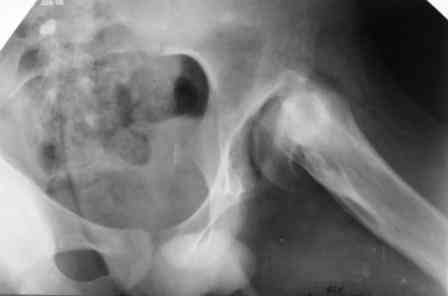

Больному 16 лет, болеет с рождения.Оперирован в детстве( корригируюшая межвертельная остеотомия с фиксацией пластиной), три года назад удалии пластину. Обратился к нам, выраженно хромота, укорочение бедра на 4 см, ходит безболезненно, отведение ограниченно при отведении и ротации. Буду рад вашим предложениям. С уважением Шухрат!

То, что Вы показали это не дисплазия, это врожденная COXA VARA.

1.D-s: Coxa vara, colly lysis,(дистрофическая Coxa vara)

2. Рентгенография левого тазобедренного сустава в положении максимального приведения бедра: если головка занимает позицию 130 градусной инклиниции (имитация положения головки при нормализации ШДУ) то, или межвертельная по Пауелсу (проще), или подвертельная с латерализацией дистального фрагмента (для относительного удлинения шейки) (подвертельная без латерализации усилит имеющийся вальгус в колене)

Если 130 градусная иклинация невозможна (нет 60 градусов приведения) тогда операция SUPER (standart utilitarian procedure extremity reconstruction) hip по Droor Paley.

3. Выполнение периацетабулярной остеотомии дискутабельное: соотношение головка-впадина несферическая инконгруентность, хотя возможно через 3-6 месяцев вторым этапом с osteochondroplasty. Одномоментно невозможно из-за большого давления головки на впадину.